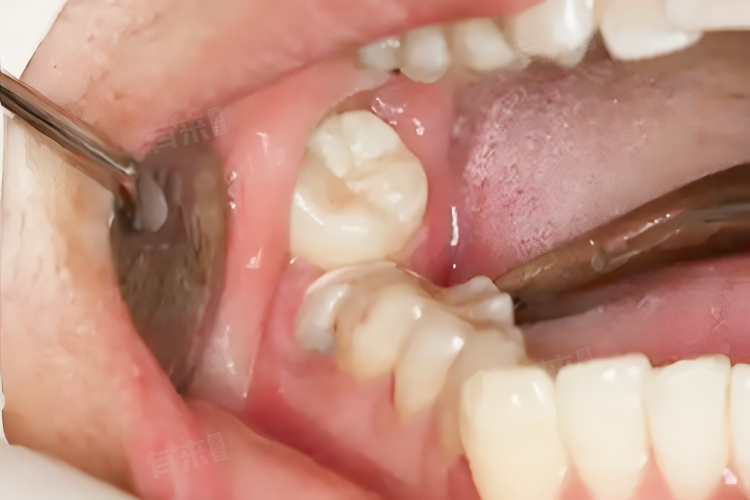

2、牙龈红肿疼痛:若智齿萌出受阻或位置不正,容易引发冠周炎,导致牙龈红肿、疼痛加剧。患者咀嚼、吞咽时疼痛明显,严重时脸颊会出现肿胀,局部淋巴结也可能肿大,此时需及时干预治疗,避免炎症扩散。

3、牙齿排列变化:智齿萌出时产生的推力,可能影响邻牙位置,导致原有牙齿排列发生改变。尤其在牙列空间不足的情况下,智齿可能挤压邻牙,造成牙齿拥挤、移位,甚至引发咬合紊乱,影响正常咀嚼功能。

4、口腔卫生问题:由于智齿位置靠后,清洁难度较大,易导致食物残渣滞留。细菌在局部滋生繁殖,不仅会引发口臭,还可能造成龋齿、牙周炎等疾病。若不及时清洁,牙齿表面会逐渐出现龋洞,牙周组织也会受到破坏。